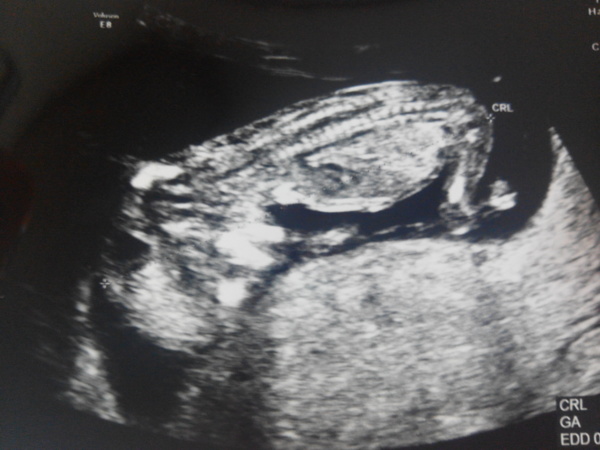

小魚兒也默默長到6公分了(好快~)

今天小魚兒是趴著的

雖然還是二頭身

但可以更明顯分得出頭跟身體

也可以清楚看到脊椎

至於手腳...醫生沒說我還是不太能看出來XD

心跳是158下/分

頸部透明帶也在正常範圍內

雖說要配合抽血檢驗才知道詳細機率

但醫生說從透明帶來看

唐式症的機率已經很低了